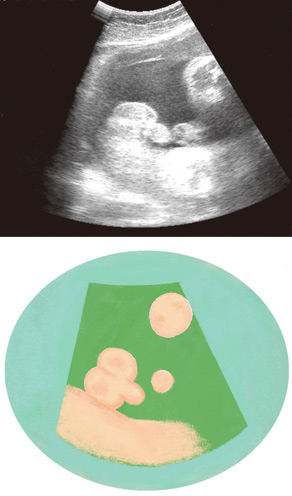

妊娠33週ころの超音波写真

体が大きくなると体位を変えにくくなります

出産が近づいて体が大きくなると、赤ちゃんは体位を変えにくくなり、外性器は見えづらくなります。性別は、外性器の特徴が確認しやすい男の子のほうが判別しやすいでしょう。